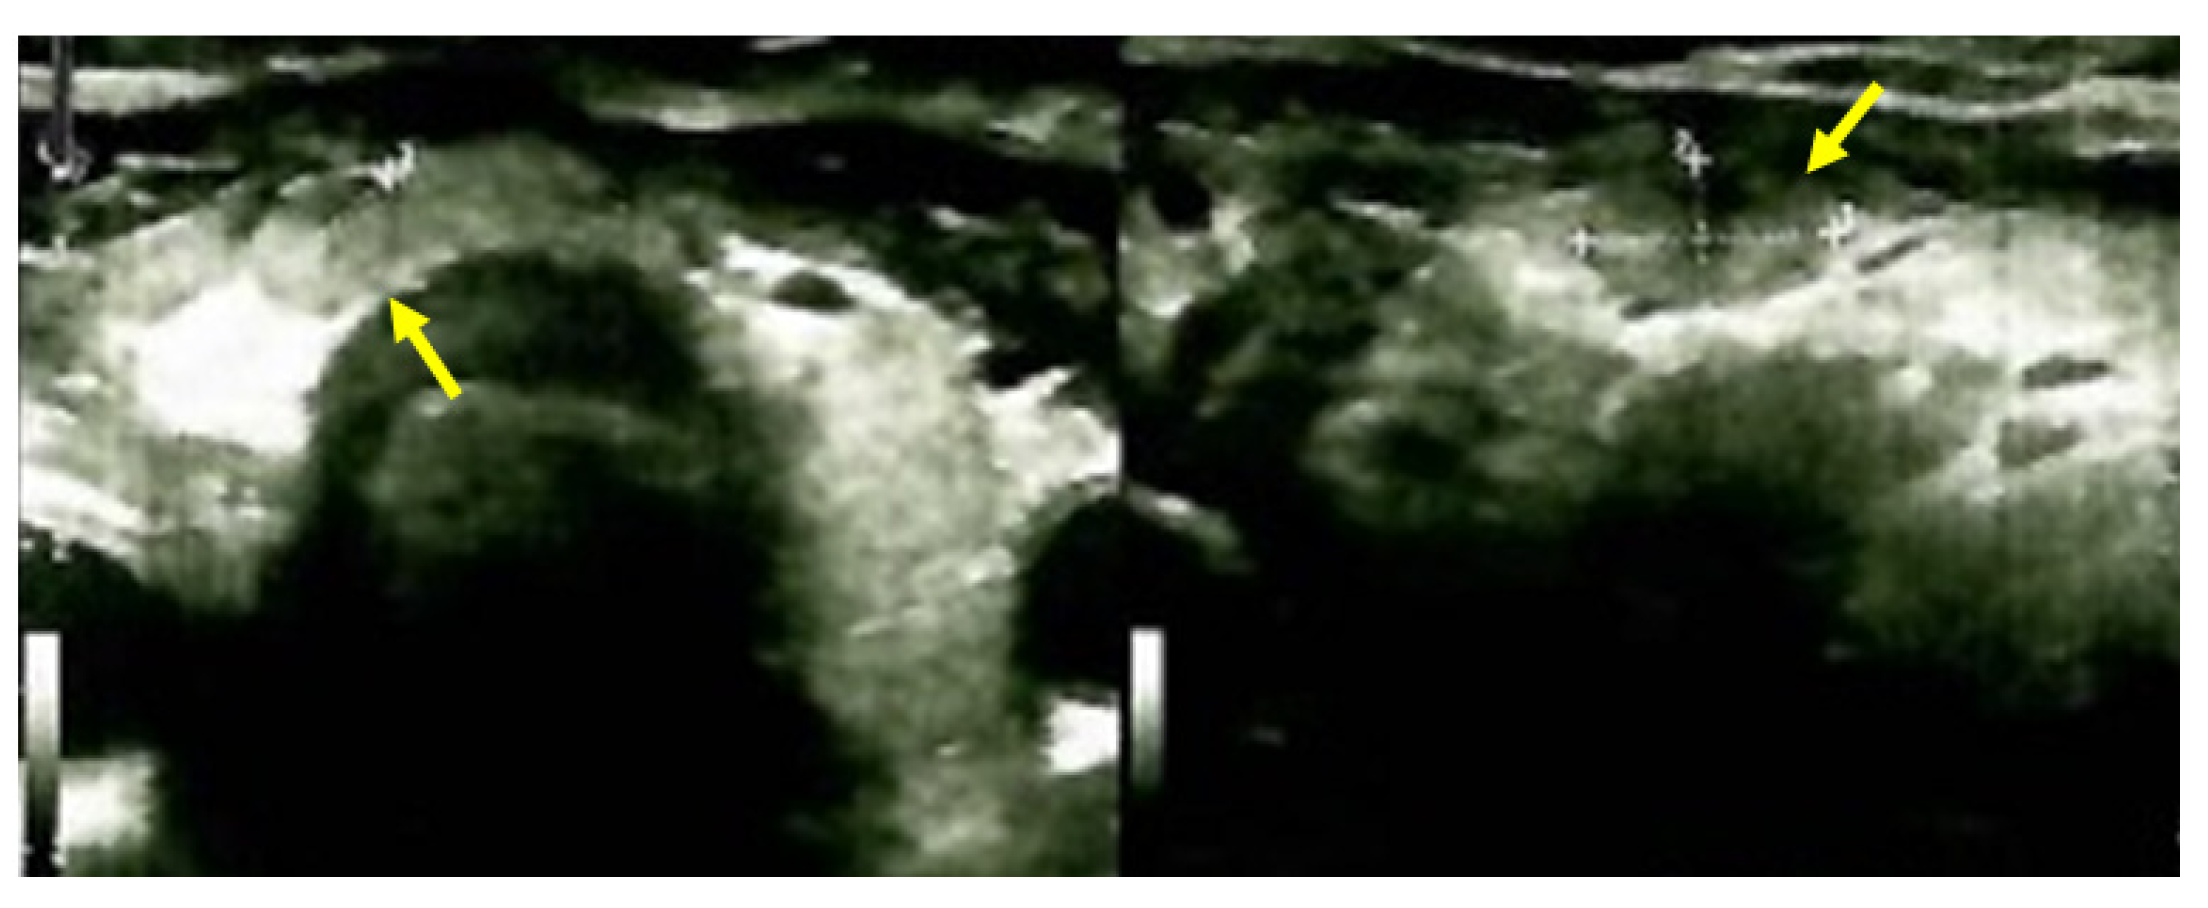

3.6. Approach of the Skull Tumors

The multidisciplinary decision (also including a neurosurgical and neurological evaluation and assessment of the tumor-associated risks and the need for a clear distinction from oncologic traits) meant that a skull tumor lesion was enucleated. The histological report showed, at the macroscopic level, brown features with a crumbly consistency and an overall apparently well-vascularized tumor. The histological exam revealed osteoclast-like multinucleated giant cells arranged on a background of fusiform cells and focal fibrosis, diffuse hemorrhage, various fragments with short and thin cancellous bone lamellae with osteoblastic activity, and areas of multiple osteoclast-related bone lysis. These lesions were consistent with the diagnosis of a brown tumor of the bone, while a malignancy was ruled out (Figure 13).

Figure 13.

Brown tumor of the skull in chronic renal disease-related severe hyperparathyroidism: typical color features at the macroscopic level that stands for the tumor’s name (left); Both center and right subfigures are microscopic exams: hematoxylin-eosin (X10).